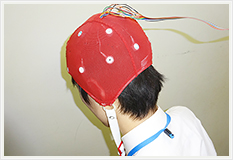

血液検査

血球計算、血液像検査、凝固線溶検査、骨髄像検査を実施しています。

血液像検査は標本を作製し、鏡検により白血球分類を行っています。

細菌検査部門

細菌検査は感染症の診断・治療に欠かせない大切な検査です。

細菌検査室では病気を起こしている病原菌を特定し、どのような治療薬(抗生剤)を使えば効果があるのかを調べています。

検査に用いる材料(検体)は喀痰・尿・便・血液・膿など体内のあらゆるものを対象としています。

塗抹染色検査

検体をスライドガラスに薄く塗り広げ染色して顕微鏡で観察します。

どんな菌が存在するか、炎症反応はあるのかを推定します。